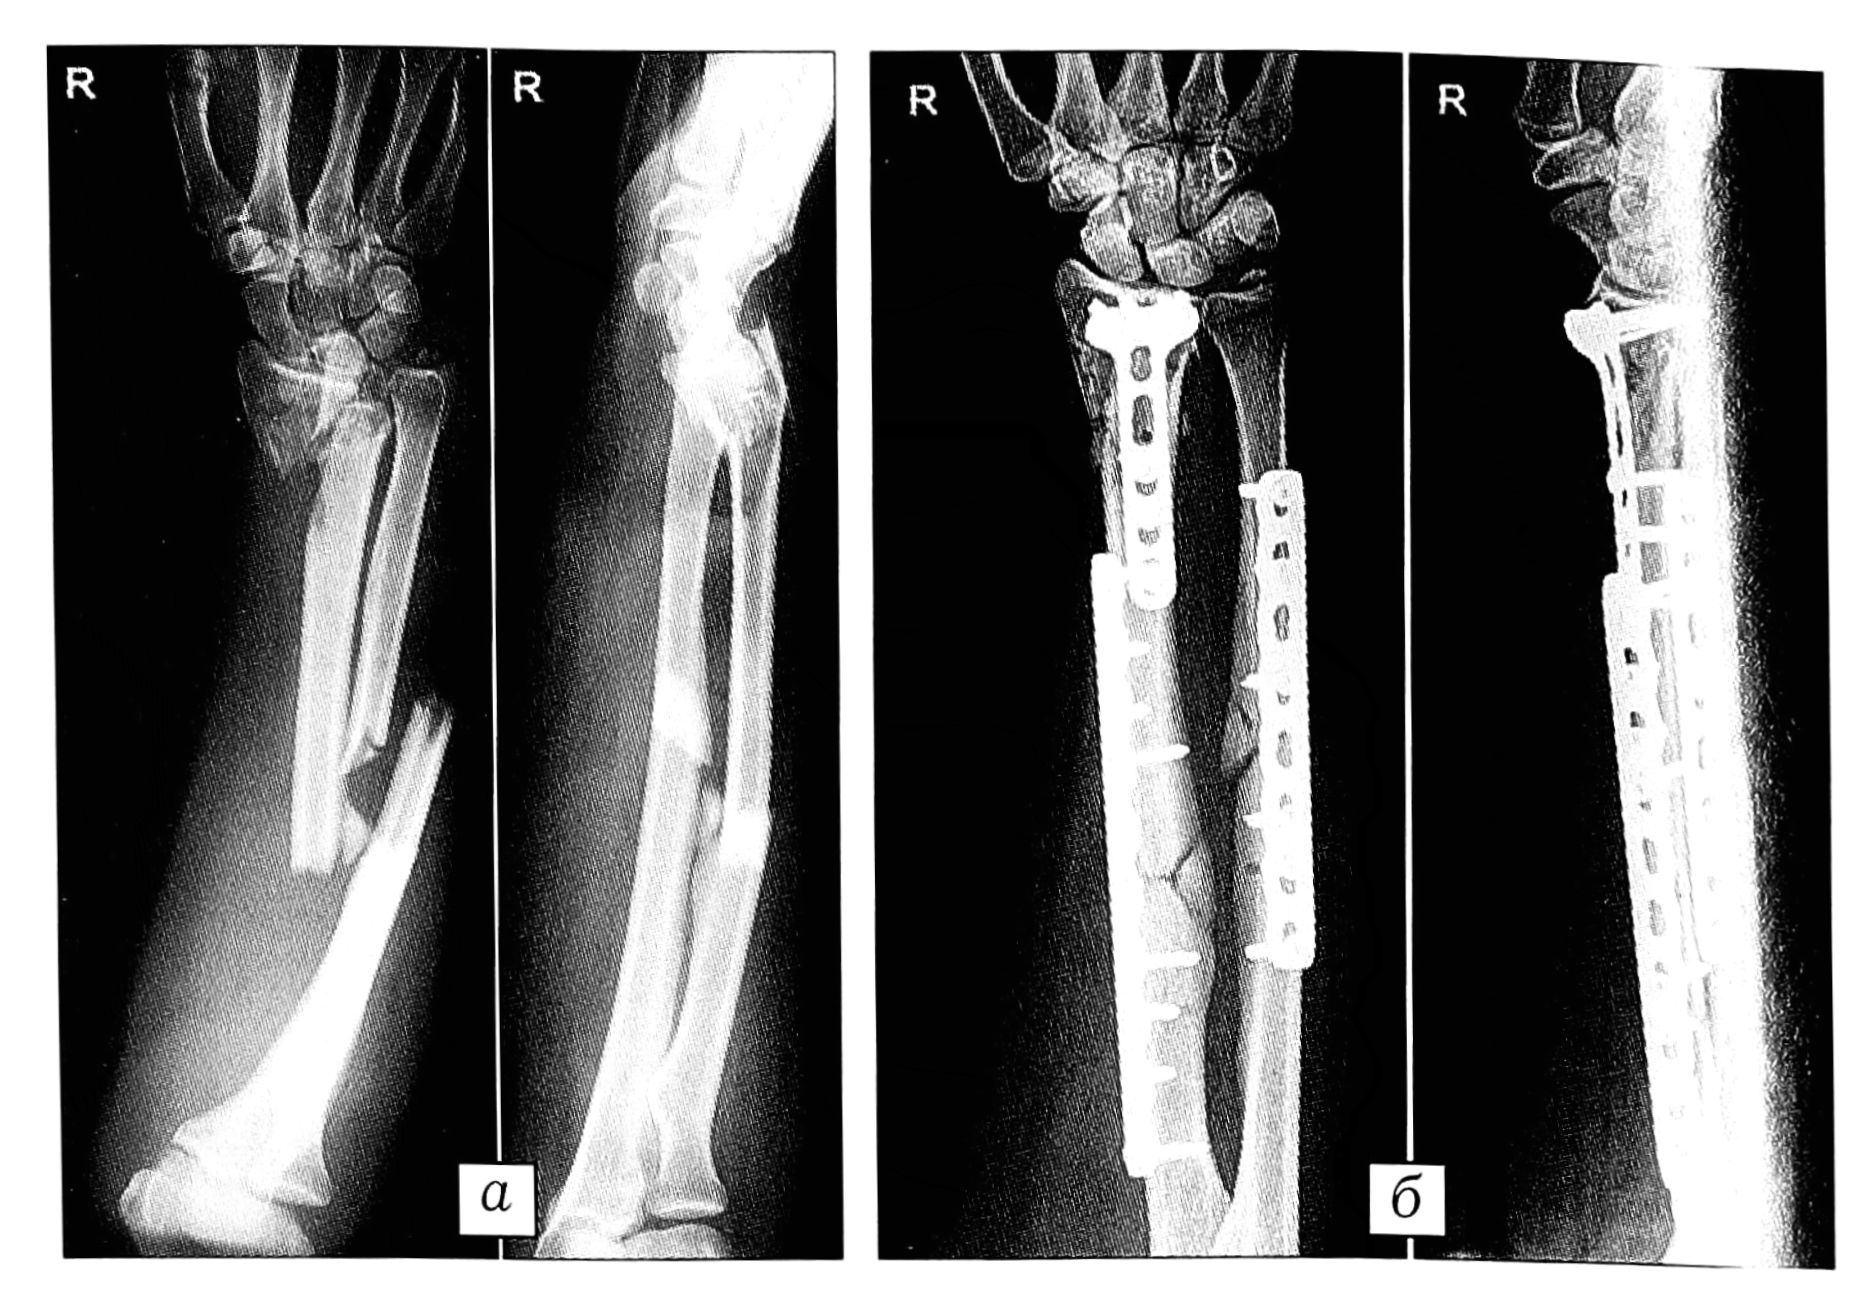

Рис. 8. Больной W. 22 лет. Политравма, полученная в результате ДТП. а — при поступлении: открытый перелом типа 22-В2 обеих костей правого предплечья и перелом типа 23-С2 дистального отдела правой лучевой кости; б — для фиксации диафизарных переломов лучевой и локтевой костей использованы 3,5 мм LCP пластины по традиционной технике компрессионного остеосинтеза, блокирующиеся винты были введены через пластины только для дополнительной фиксации. В дистальном отделе лучевой кости для «перемыкания» раздробленной метафизарной зоны использована только 3,5 мм LCP Т-образная пластина после анатомического восстановления суставных поверхностей.